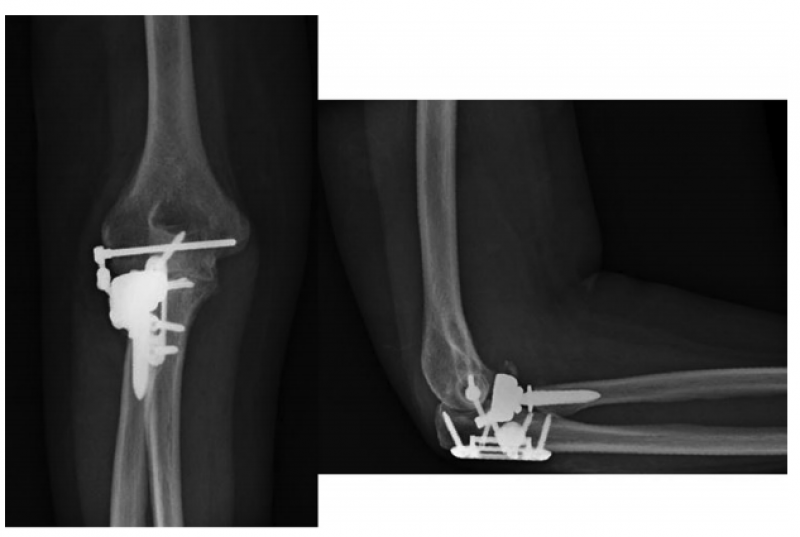

7、Pasternack等提出了一种型的肘关节内固定架,只有10例患者(6例是三联征,2例新鲜肘关节脱位,1例陈旧肘关节脱位,1例外髁骨折),2016年获得FDA批准。平均术后74天后取出。内固定架能够减少外固定架带来的术后并发症,同时能够维持肘关节的稳定性,但由于初始损伤比较重,由于其他各种原因导致的二次手术率仍然较高。